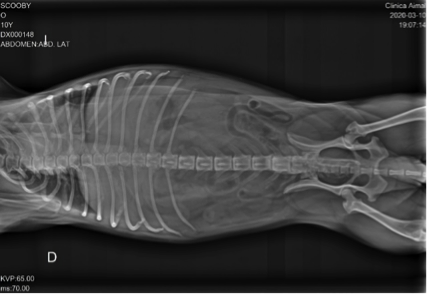

Después de revisar completamente a Scooby, nos cercioramos del fuerte dolor abdominal que efectivamente presenta. La auscultación es aparentemente normal y su temperatura de 38,4ºC. Se le recomienda la realización de radiografías de abdomen y columna (para descartar una posible discoespondilitis).

Observamos que la columna es aparentemente normal, pero podemos ver urolitos en la vejiga de la orina.